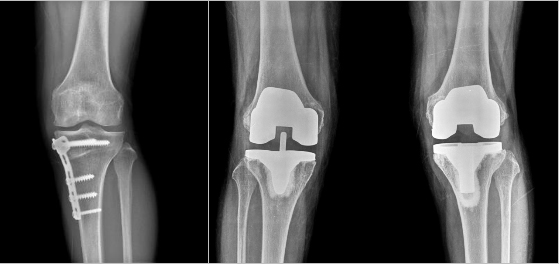

4) 수술적 치료 심한 통증이 지속되거나 관절의 불안정성, 변형 및 운동 제한 등이 진행하면 수술적 치료의 적응이 됩니다. 수술 치료는 관절경을 이용한 세척술 및 변연 절제술부터 하지의 내반 또는 외반 변형을 교정해주는 절골술, 그리고 고령의 심한 관절염 환자에게 시행하는 인공 관절 치환술 까지 많은 방법이 있으며, 환자의 나이와 기대활동 수준, 골관절염의 정도, 이환된 슬관절 구획의 수, 하지 정렬 상태 등 여러 요인을 고려하여 선택합니다.